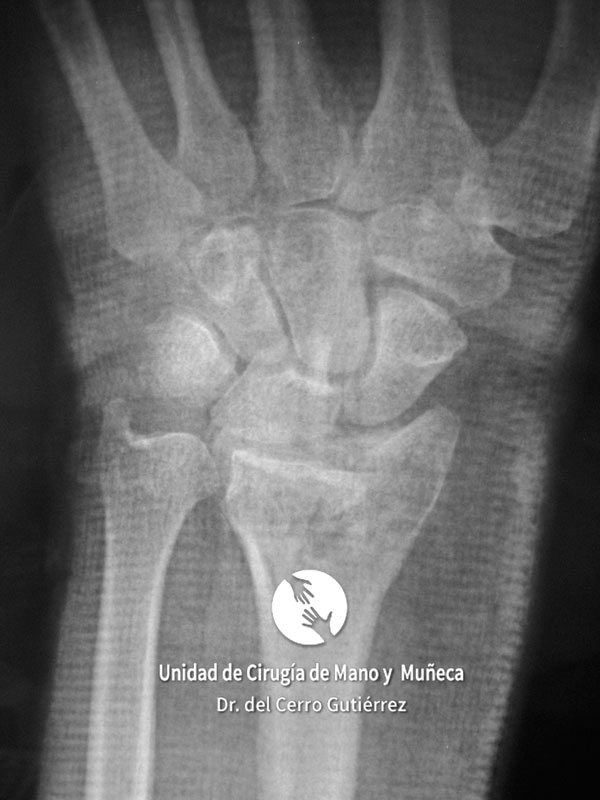

Imágenes de diagnótico de fracturas del radio distal de la muñeca

Fractura del Radio. Avulsión Estiloides.

Fractura del Radio. Desplazamiento Dorsal.

Fractura del Radio. Fractura Extraarticular

Fractura del Radio.

Fractura del Radio. Fractura del Escafoides.

Fractura del Radio. Conminuta y Articular.